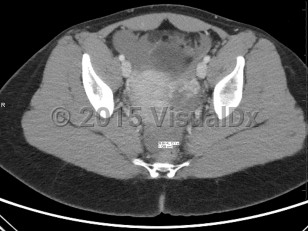

Ruptured ectopic pregnancy can result in intraperitoneal bleeding, uterine hemorrhage, and hemodynamic instability. Development of any of these complications should be considered a surgical emergency and warrants emergent evaluation by a gynecologic surgeon; exploratory laparotomy may be required. Even in the absence of concern for rupture, surgery may be considered, particularly in patients failing or with contraindications to methotrexate, in the setting of heterotopic pregnancy (ectopic pregnancy occurring simultaneously with a viable intrauterine pregnancy; see Look For), or in patients seeking sterilization.

A 2011 consensus statement provides definitions that draw attention to the complexity of evaluating for and diagnosing ectopic pregnancy, with 5 categories based on sonographic findings:

- Definitive intrauterine pregnancy

- Probable intrauterine pregnancy

- Pregnancy of unknown location

- Probable ectopic pregnancy

- Definite ectopic pregnancy